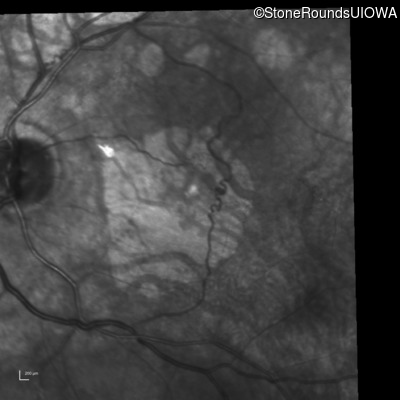

Infrared Fundus Photograph - Right - 20/100 +1 sc

Exemplar